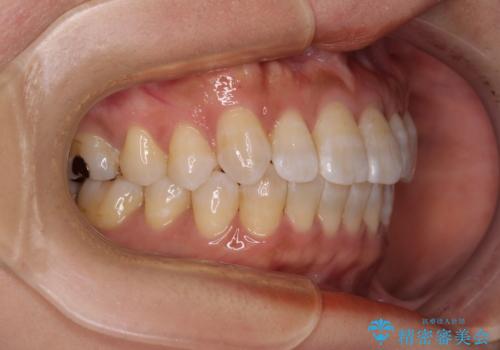

気になる八重歯 ワイヤー装置での非抜歯矯正

- 上顎の八重歯と全体的なデコボコを気にして来院された患者様です。

口元の突出感はなかったため非抜歯矯正での対応となりますが、八重歯を改善する際に上顎前歯が前突する可能性があったため、上顎臼歯部にアンカースクリューを使用して、歯列が前方に転位しないようにすることとしました。